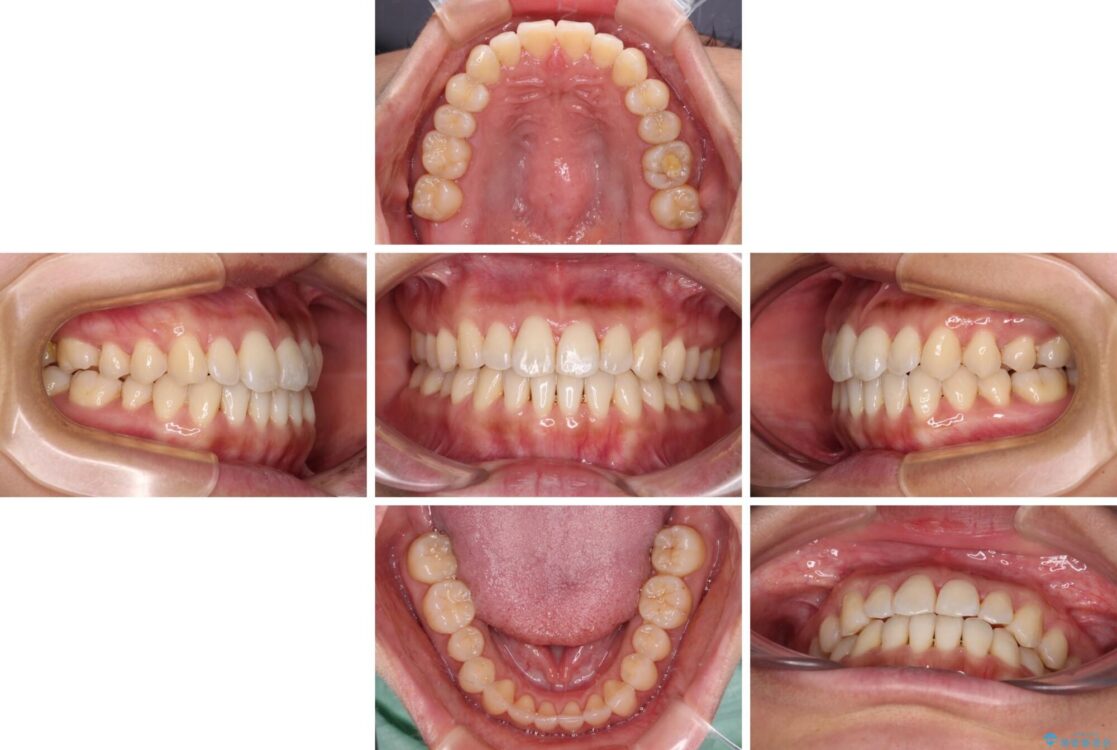

前歯のデコボコで前方に出ていることを気にして来院された患者様です。

治療計画

上顎前歯が捻れて前方に飛び出しており、下顎前歯もそれに沿うようにデコボコとなっていました。

IPR(歯と歯の間を削る処置)によりスペースを獲得して上下顎前歯のデコボコを改善し、飛び出している前歯が引っ込むように設定し、インビザラインにて矯正治療を行うこととしました。

治療後について

装着時間を守ってくださったので、予定通りの期間で終えることができました。インビザライン特有の、奥歯の咬み合わせの問題もなく、しっかりと歯列を改善することができました。

治療前

治療後